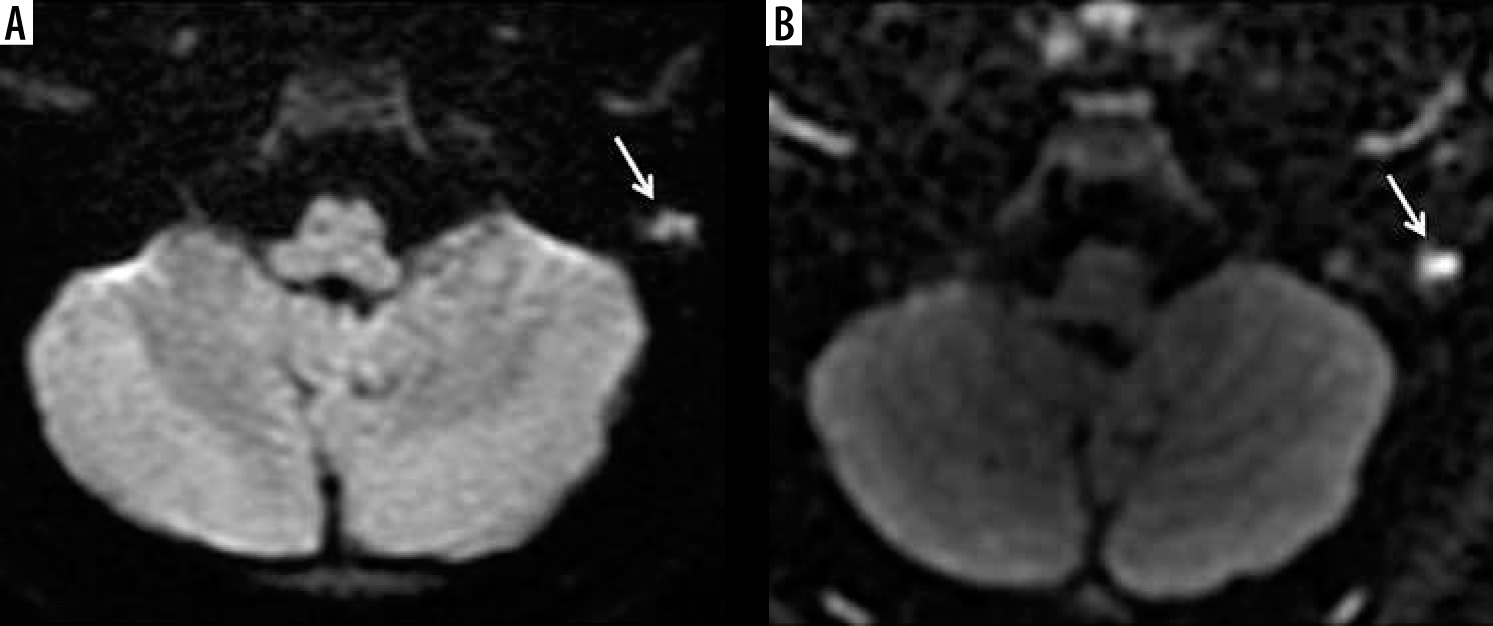

Figure 2

The example of worse diagnostic value of echo-planar imaging (A) compared to non-echo-planar (B) diffusion-weighted imaging in depicting middle ear cholesteatoma (arrows)